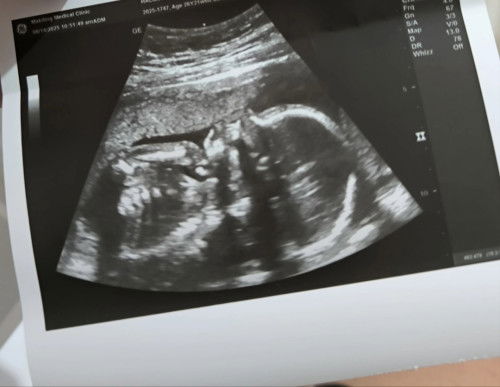

Normal kaya ang lipt and nose ni baby?

hindi paalinaw if normal yung nose and lips ni baby base sa ultrasound kahapon. masyado kasing nakadikit sa placenta kaya di pa malinaw. As a first time mom, na halos lahat ng payo ng OB is sinusunod. Nakakabothered pa rin pag di pa nakalagay sa result ang "normal" sana normal lahat kay baby 🤞 #firsttimemom #pregnancy #AskingAsAMom